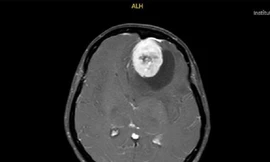

Từ khóa: "Chẩn đoán và điều trị u não"